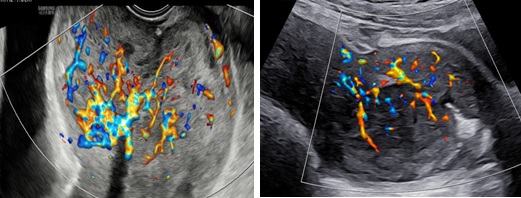

Hình 2: Trên Doppler màu, khối trong lòng tử cung tăng sinh mạch máu mức độ 2

Hình 3: (trái: ngã âm đạo, phải: ngã bụng): Trên Dopple màu, phần tổn thương ở cổ tăng sinh mạch máu độ 4, không ranh giới giữa tổn thương và cơ vùng cổ tử cung